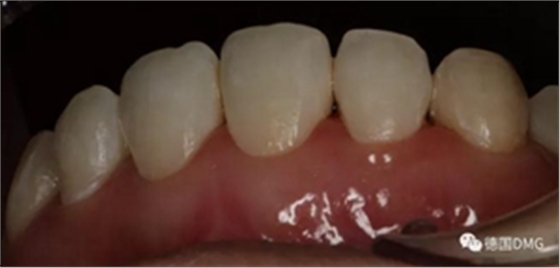

術后顯示,滲透樹脂恢復了天然牙釉質的折光率(天然通透牙釉質折光率1.62滲透樹脂折光率是1.52)顯的很自然,很有光澤。完全是天然牙質的顏色。

(下圖是拋光完成)

治療完成的上頜牙齒和未治療的下頜牙齒形成明顯對比。

治療前和治療后的對比,患者很高興很滿意。